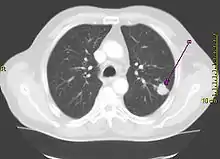

Le cancer du poumon peut être vu sur les radiographies thoraciques et le scanner. Le diagnostic est confirmé par une biopsie. Ceci se fait généralement par bronchoscopie, ou par biopsie guidée par scanner. Le traitement et le pronostic dépendent du type histologique du cancer, de son stade (degré de dissémination), et de l'état général de santé du patient.

La radiographie thoracique est la première mesure à prendre si un patient se plaint de symptômes pouvant suggérer un cancer du poumon. Ceci peut révéler une masse évidente, un élargissement du médiastin (qui suggère une extension aux ganglions lymphatiques qui s'y trouvent), une atélectasie (affaissement), une inflammation (pneumonie) ou un épanchement pleural. En l'absence de signes radiographiques, mais si les soupçons sont élevés (par exemple, un gros fumeur avec hémoptysie), une bronchoscopie ou un scanner peuvent donner l'information nécessaire. La bronchoscopie ou la biopsie guidée par scanner sont souvent utilisées pour identifier le type de tumeur[3].

Si les examens confirment le cancer du poumon, le scanner et souvent la tomographie par émission de positons (TEP) sont utilisés pour déterminer si le cancer est localisé et possible à traiter par chirurgie, ou bien s'il s'est étendu au point de ne plus pouvoir être éliminé par la chirurgie. Des tests sanguins et la spirométrie (test de la fonction respiratoire) sont également nécessaires pour déterminer si le patient va assez bien pour supporter l'opération. Si la spirométrie révèle une faible réserve respiratoire (souvent due à un trouble ventilatoire obstructif), la chirurgie peut être contre-indiquée.

L'opération chirurgicale en elle-même a un taux de décès d'environ 4,4 %, en fonction de l'état des poumons du patient et d'autres facteurs de risque[148]. La chirurgie est d'habitude seulement une option sur les carcinomes non à petites cellules, limités à un seul poumon, jusqu'au stade IIIA. Ceci est déterminé par imagerie médicale (scanner ou TEP). Une réserve respiratoire préopératoire suffisante doit être présente, pour permettre au poumon de fonctionner correctement après résection du tissu.